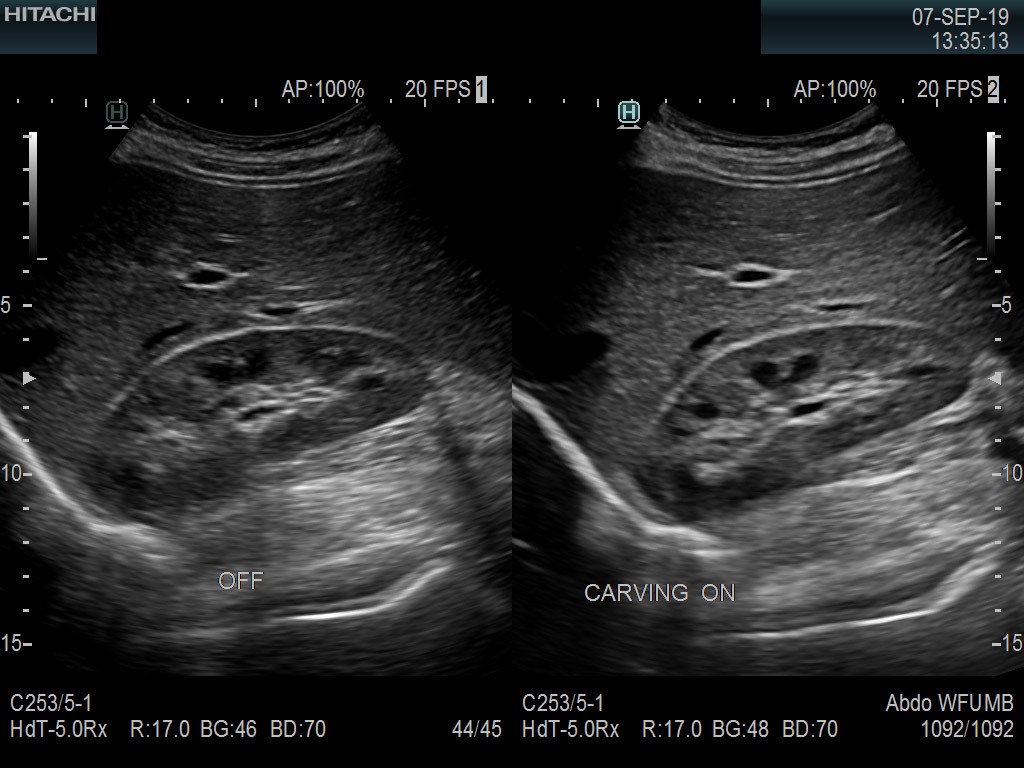

Fujifilm Healthcare’s ARIETTA Precision features state-of-the-art digital architecture and advanced imaging technologies to redefine the capabilities of surgical ultrasound.

Imaging Clearly Defined

State-of-the-art digital architecture and advanced imaging features to redefine the capabilities of surgical ultrasound.